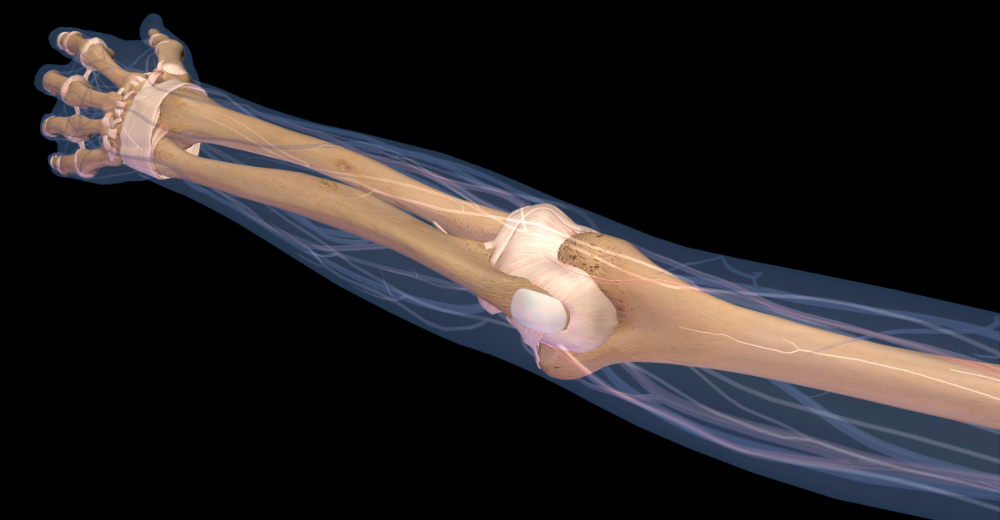

L’Esame RX Braccio, comunemente conosciuto come radiografia del braccio, è un esame diagnostico che utilizza un basso dosaggio di radiazioni ionizzanti per ottenere immagini nitide delle ossa e delle articolazioni del braccio. Si tratta di una procedura non invasiva e indolore, indicata per valutare diverse condizioni patologiche e traumi che possono interessare questa zona del corpo. Le immagini ottenute forniscono informazioni cruciali sulla struttura ossea e permettono di identificare tempestivamente la presenza di lesioni o anomalie.

Cosa Si Può Diagnosticare con l’Esame RX Braccio?

L’Esame RX Braccio permette di rilevare numerose condizioni patologiche e traumi che interessano il braccio, tra cui:

• Fratture ossee: identificazione di fratture evidenti o microfratture.

• Lussazioni e sublussazioni: verifica dell’integrità delle articolazioni e della loro posizione.

• Artrosi: valutazione della degenerazione delle articolazioni e del livello di compromissione ossea.

• Tumori ossei: identificazione di masse sospette o lesioni a carico dell’osso.

• Anomalie congenite: come malformazioni o sviluppo anomalo delle strutture ossee.